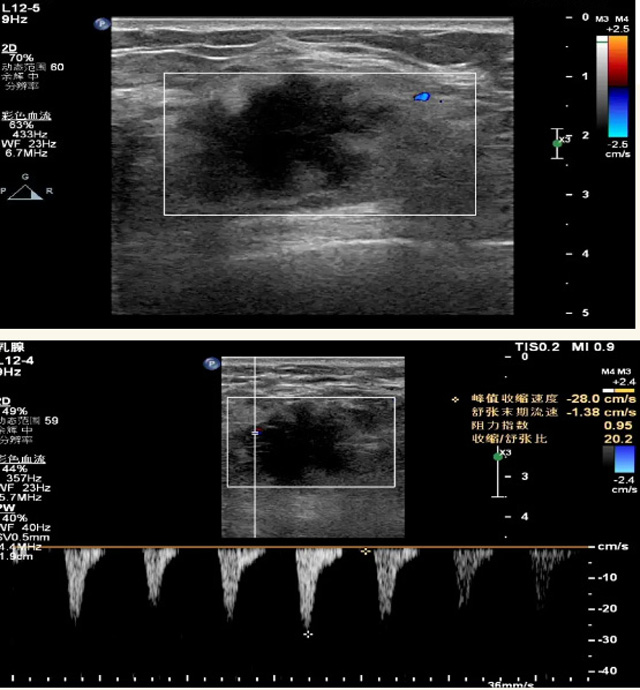

乳腺B超檢查無輻射,對囊性病變敏感,可以實時觀察病灶。超聲引導活檢跟手術前的定位。就是它對于微小的鈣化查出率比鉬靶稍微差點。磁共振MRI檢查也是是沒有輻射的,對備孕跟已經懷孕的人士比較友好。不用擔心這個輻射影響胎兒問題。對乳腺病灶敏感性較高,致密乳腺病灶、乳腺癌的復發(fā),準確鑒別囊性及實性病變。可以幫助臨床醫(yī)生判斷惡性、良性病變。但是MRI磁共振對微小鈣化不明顯,微鈣化還是鉬靶靠譜點。檢查時間比較長,有偽影的影響。費用相對B超,鉬靶高很多。

乳腺B超